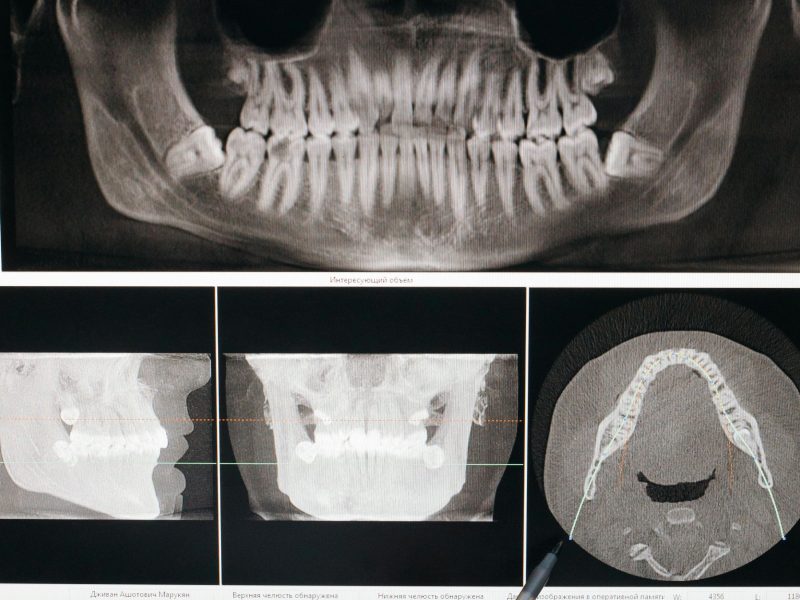

Протезирование зубов — это стоматологическая процедура, которая проводится с целью восстановления утраченных зубов с помощью искусственных заменителей. Зубные протезы бывают как съемными, так и несъемными, в зависимости от индивидуальных потребностей пациента.Протезы позволяют восстановить полноценное жевание, что способствует улучшению пищеварения и общего состояния здоровья. Современные конструкции выглядят естественно, что позволяет вернуть уверенность в себе и улучшить внешний вид. Протезирование помогает исключить смещение соседних зубов, что приводит к дополнительным проблемам с прикусом и жеванием. Потеря зубов влияет на произношение. Протезы восстанавливают четкость речи. Современные материалы и технологии обеспечивают долговечность протезов, что делает их выгодным вложением.Если вы столкнулись с проблемой утраты зубов, не откладывайте визит к стоматологу.